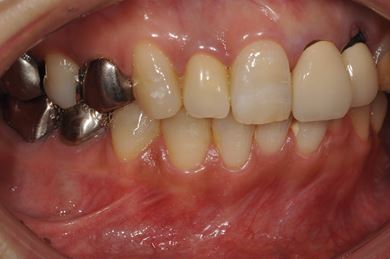

インプラントの症例写真 IMPLANT

骨再生インプラント治療+セラミック治療

| カテゴリー | 【インプラント治療】【セラミック治療】 | ||||||||||||||||||||||||||||||||

| 性別/年齢 | 女性 / 48歳 | ||||||||||||||||||||||||||||||||

| 主訴 | 他の歯科で、前歯の差し歯が折れたところにインプラントをすすめられているので、費用や期間など知りたい。 | ||||||||||||||||||||||||||||||||

| 治療方針 | 骨再生法により、インプラント治療を可能にする。 | ||||||||||||||||||||||||||||||||

| 治療内容 | インプラント1本、メタルボンドセラミッククラウン2本、GBR | ||||||||||||||||||||||||||||||||

| 総治療費 | 618,660円 | ||||||||||||||||||||||||||||||||

| 治療期間 | 9ヶ月 |